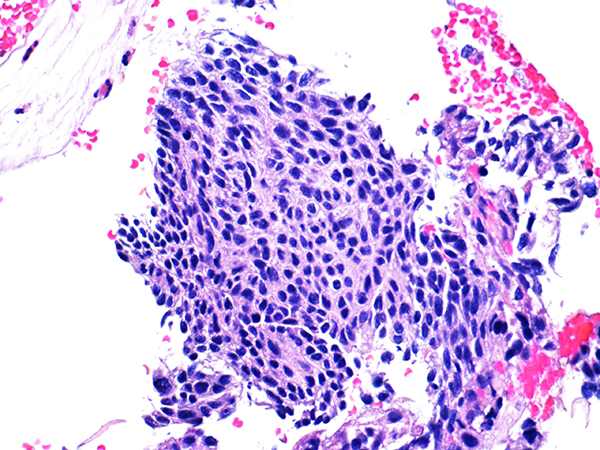

![]() Case 1

Area 1 - Soft Bx CIN 2 40x - High Power |